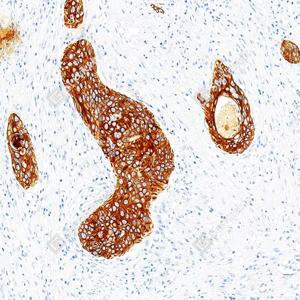

IHC检测Cytokeratin 1蛋白(货号 GB151018). 样品: 人喉鳞状细胞癌, 4%多聚甲醛 (货号G1101) 固定12-24小时. 抗原修复: 柠檬酸抗原修复液(干粉, pH 6.0) (G1201), 高压锅均匀喷气计时2分钟. —抗: 1: 1000稀释, 4℃ 孵育过夜. 二抗: S-vision免疫组化多聚二抗(山羊抗兔),即用型 (货号G1302), 室温孵育20分钟. |

|